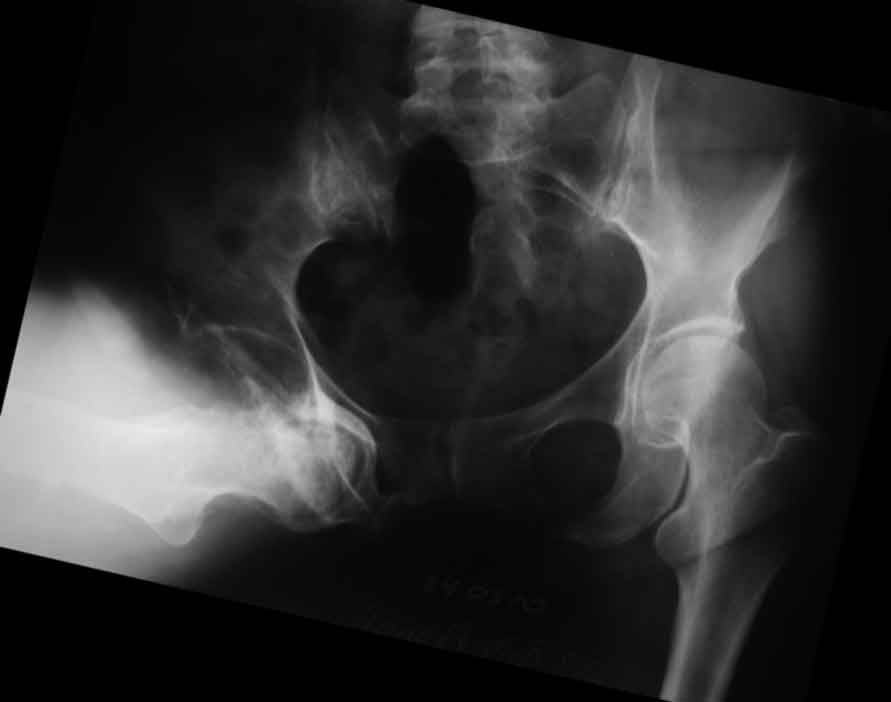

В отделение поступила пациентка 57 лет с застарелым запирательным вывихом правого бедра. Травма 7 лет назад, упала в лесу, местный врач вправление выполнить не смог, отправил жить так. По разным причинам поступила для протезирования сейчас. Движения в неоартрозе есть неплохие за исключением разгибания (с/р 120/90/0), коленный сустав с/р 140/10/0. Значимой неврологии не определяется Планируется цементное эндопротезирование. Уважаемые коллеги, поделитесь специфическими трудностями, с которыми сталкивались в подобных случаях. С уважением, Максим Агалаков, Е-бург.

пока сложно сделать нормальный снимок после операции, это первый